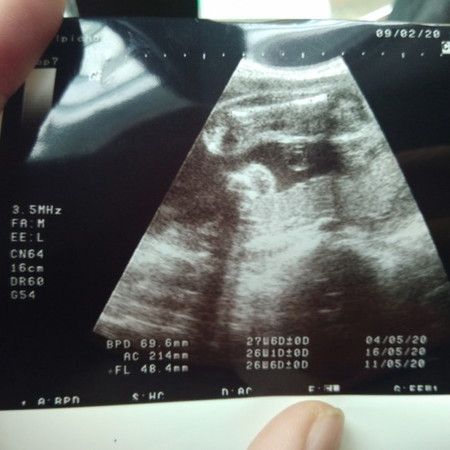

ดูยังไงคะว่า ญ หรือ ช. แม่ดูไม่ออกจริงๆ?

ขา 2ข้างของน้อง ค่ะ ช่องกลางระหว่างขา มองไม่เห็นไข่หรือจู๋น้อย มันราบเรียบ เป็นกลีบๆน่าจะ ญ ค่ะ

เหมือนผู้หญิง มากกว่านะ เพราะของเราผู้ชายจะมีไข่ออกมาด้วย

เหมือนผู้หญิงค่ะ เหมือนเห็นเป็นกลีบค่ะ

น่าจะผู้หญิงจ้า ถ้าชาย คงมีจุ๊ดจู๋โผล่

น่าจะ ญ ไม่มีมีตออะไนโผ่มา

ดูจากภาพผู้หญิงนะค่ะ